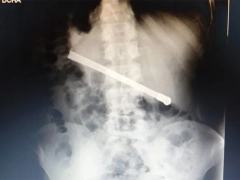

La radiografía mostró que tenía una bombilla

Un preso que se encuentra alojado en el Complejo Penitenciario Rosario (CPR) se tragó una bombilla de mate y tuvo que ser operado en el hospital Eva Perón. El hombre, de 35 años, tenía el objeto atravesado en el tórax y fue intervenido quirúrgicamente este martes.

Al continuar con el malestar, le realizaron una placa radiográfica en la Unidad Penitenciaria ubicada en 27 de Febrero al 7800, y pudieron determinar que había ingerido una bombilla de mate que quedó alojada transversalmente en la cavidad torácica.